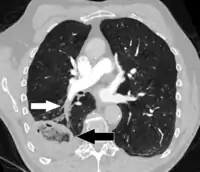

Pulmonary embolism (white arrow) that has been long-standing and has caused a lung infarction (black arrow) seen as a reverse halo sign.